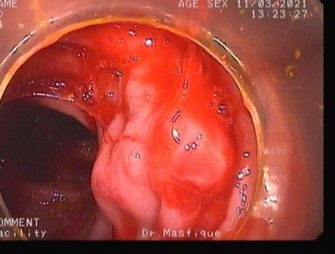

Colonoscopy image datasets are inherently heterogeneous, containing frames acquired under a variety of clinical conditions. As illustrated in Table 4, the data frequently exhibit artifacts that complicate polyp detection and segmentation. Examples include stool residues adhering to the intestinal wall, blood obscuring mucosal surfaces, or inflammation that alters tissue appearance. Additional challenges arise from image acquisition itself, such as low brightness, chromatic aberration, motion blur, or the presence of surgical tools in the field of view.

Table 4: Challenging Polyp image examples of BPD dataset.

Sl. no Image description Image Mask

1 Image containing polyp without any noise or challenging aspects [Uncaptioned image] [Uncaptioned image]

2 Image contains polyp with some stool dotting the intestinal wall [Uncaptioned image] [Uncaptioned image]

3 Image contains polyp with blood being present on the intestine wall [Uncaptioned image] [Uncaptioned image]

4 Image contains polyp in an inflamed intestine [Uncaptioned image] [Uncaptioned image]

5 Blurred or unfocused image containing polyp [Uncaptioned image] [Uncaptioned image]

6 Chromatic aberration distortion present in polyp image [Uncaptioned image] [Uncaptioned image]

7 Low brightness image containing polyp [Uncaptioned image] [Uncaptioned image]

8 Image with improper bowel preparation [Uncaptioned image] [Uncaptioned image]

9 Surgical tool present alongside polyp [Uncaptioned image] [Uncaptioned image]

10 Motion blur present in image [Uncaptioned image] [Uncaptioned image]